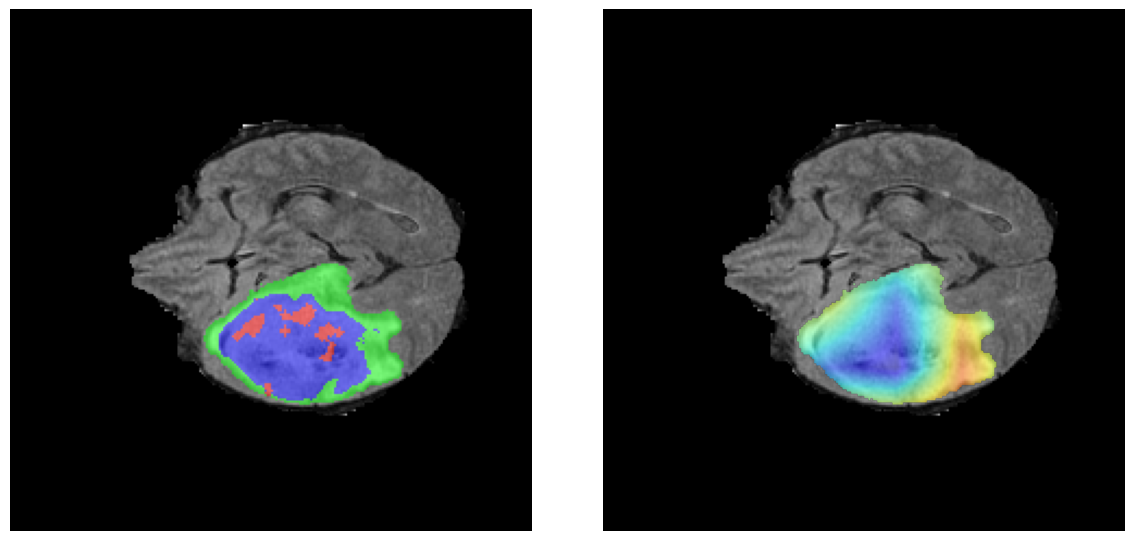

Mapas de Explicabilidad (Grad-CAM++)

Visualización de las regiones de atención del modelo que validan su razonamiento clínicamente relevante

Ejemplos HGG - Atención en Núcleo Necrótico y Tumor Realzado

HGG Grad-CAM++ 1 HGG Grad-CAM++ 2 HGG Grad-CAM++ 3 HGG Grad-CAM++ 4 HGG Grad-CAM++ 5 HGG Grad-CAM++ 6

Los heatmaps muestran que el modelo concentra su atención en las regiones de Tumor Realzado (rojo) y Núcleo Necrótico (azul), características patológicas clave de los gliomas de alto grado.